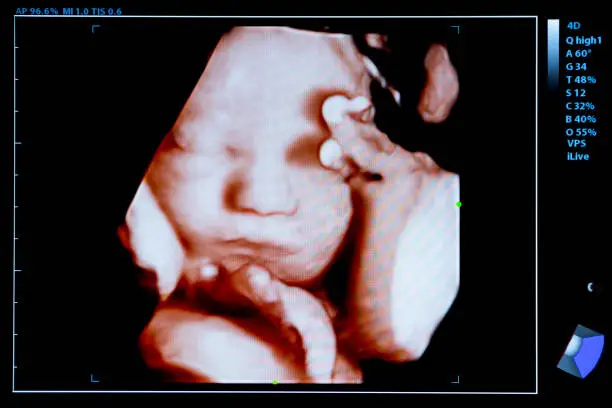

이러한 경우, 초음파 검사나 혈액 검사를 통해 정확한 진단을 받는 것이 필요합니다. 또한 출혈이 지속될 때는 스트레스나 과도한 활동을 피하고, 휴식을 취하는 것이 좋습니다. 이는 몸이 회복하는 데 도움을 줄 수 있으며, 불필요한 추가 출혈을 방지할 수 있습니다. 그러나 출혈이 계속될 경우 의사와의 상담을 통해 적절한 치료 방안을 모색해야 합니다.